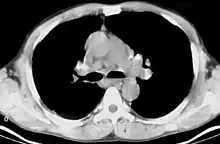

CT scan of the chest showing bilateral lymphadenopathy in the mediastinum due to sarcoidosis.

Bilateral hilar lymphadenopathy is a bilateral enlargement of the lymph nodes of pulmonary hila. It is a radiographic term for the enlargement of mediastinal lymph nodes and is most commonly identified by a chest x-ray.